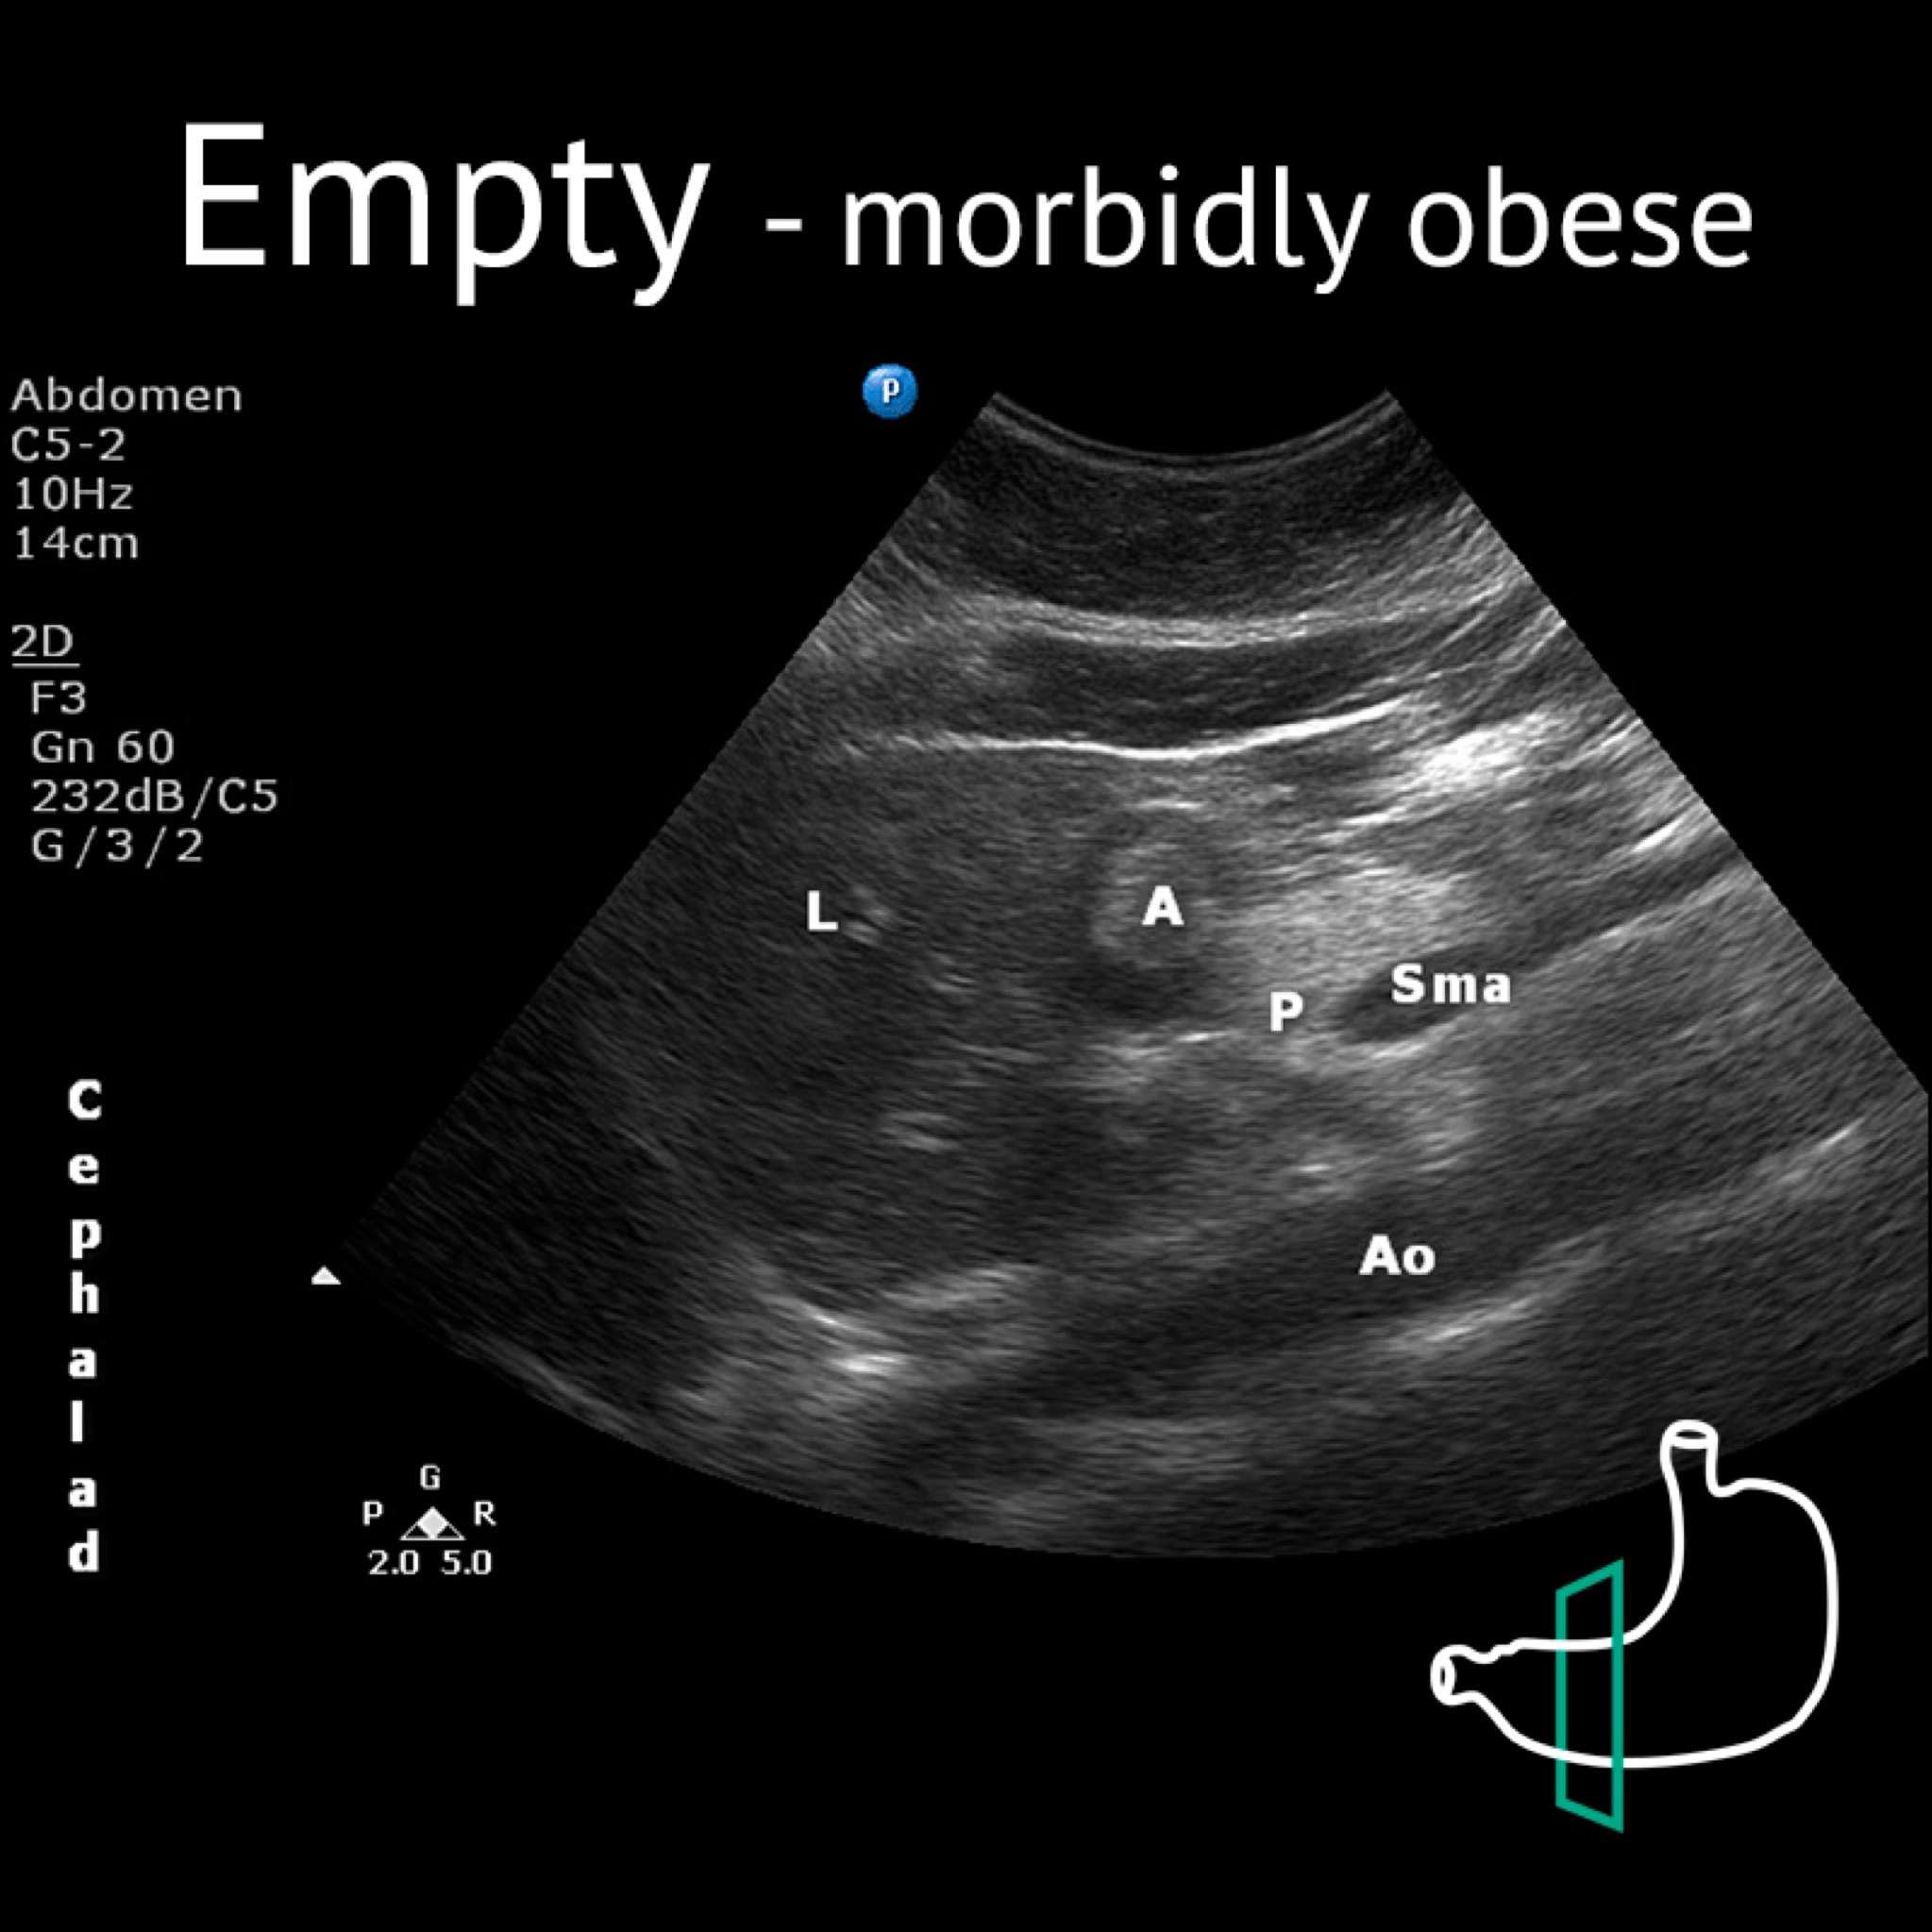

A: antrum; Ao: aorta; L: liver; P: pancreas; Sma: superior mesenteric artery